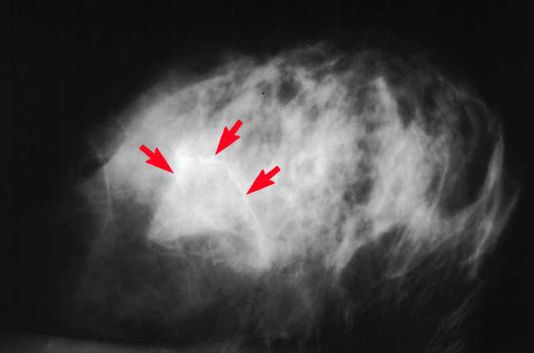

乳房动脉钙化是钙累积在乳房动脉壁的中层。它和老化、第二型糖尿病、高血压和发炎相关,是动脉硬化的标志。但和动脉内层钙化并不相同 (内层接触血液),那是抽烟和高胆固醇的人常有的。乳房动脉钙化在乳房摄影中出现在乳房动脉里的白色斑块,和癌症不相干。

此研究结果发现:乳房摄影中有乳房动脉钙化的妇女,比没有乳房动脉钙化的妇女,多51%可能发生心脏病或中风,多23%可能发生任何一种类型的心血管疾病,包括心脏病、中风、心脏衰竭和周边动脉的疾病。

乳房摄影中有乳房动脉钙化的妇女,比没有乳房动脉钙化的妇女,多51%可能发展出心脏病或中风。

乳房动脉钙化的妇女,多23%发展出任何一种类型的心血管疾病,包括心脏病、中风、心脏衰竭和周边动脉的疾病。